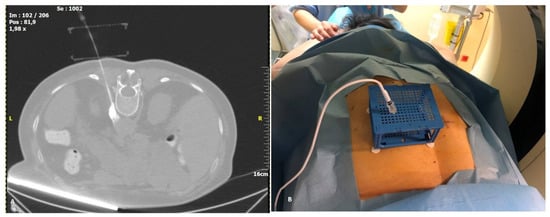

Figure 3. Planning of the puncture: (A): The yellow line represents the planned puncture path via a virtual needle (markers on the line represent cm). (B): The software calculates the entry (upper plate left) and exit point (lower plate right) and displays green dots at the coordinates to be used for this particular planned line.

The CT images are sent to the dedicated software “Synedra View Professional” (Synedra information technologies GmbH, Innsbruck, Austria) via PACS. The software recognizes the location of the PC on the patient’s skin, and a virtual model of the cube is created. Then, 3D MPR reconstructions and a virtual needle path are used by the operator for selection of target approach through the PC. Once a path is chosen, the corresponding holes on both the upper and lower surfaces are indicated by green dots on the virtual cube, as well as in the 3D MPR view. As the virtual needle has distance markers, using puncture needles with distance indicators allow for control of the puncture depth (Figure 3A). To achieve accuracy in the insertion of the puncture needle, the software automatically places the path of the virtual needle in one corner of the indicated hole. Next, the operator introduces the puncture needle into the determined coordinates on both layers of the PC. Sequential control scans are performed until the needle reaches the target.

2.3. Puncture Description

Patients were placed in prone position on the CT table. Prior to radio frequency ablation all patients were sedated with incrementally increasing i.v doses of fentanyl and propofol. Vital signs were monitored throughout the procedure, including oxygen saturations and ECG. Computed tomography sequential scans (120 Kv, 240 mAs wavelength and 2 mm slice thickness) were performed for planning, targeting and intra-procedural modification. Based on a lateral and an antero-posterior topogram at the 12th thoracic vertebral body (TH12), the approximate puncture site was marked on the skin. After skin disinfection, the PC was placed over the approximate puncture site and a CT planning scan was obtained during breath hold of the patient. The images were transferred to the software as described above and the access route to the target, antero-lateral on the TH12 vertebral body, was determined. The coordinates to introduce the needle were recorded for the upper and lower plate (Figure 3B). A 15 cm long, 20–gauge radiofrequency needle with a 10 mm active tip (Diros OWL® RF Probe, Diros Technology Inc., Ontario, ON, Canada) was inserted and its approach until the level of splanchnic nerve plexus antero-lateral to the vertebral body was evaluated with sequential CT scans until the designated target was reached. The cube was collapsed, as designed, after the needle was firmly introduced a few centimeters into the patient. The neurolysis session was performed with an ablation protocol according to the manufacturer’s guidelines (two circles of 90 s at a temperature between 80–90 °C) (Figure 4A). Patients remained in the hospital overnight before discharge. All five procedures were performed by two highly experienced interventional radiologists who had no prior experience with the CNS.